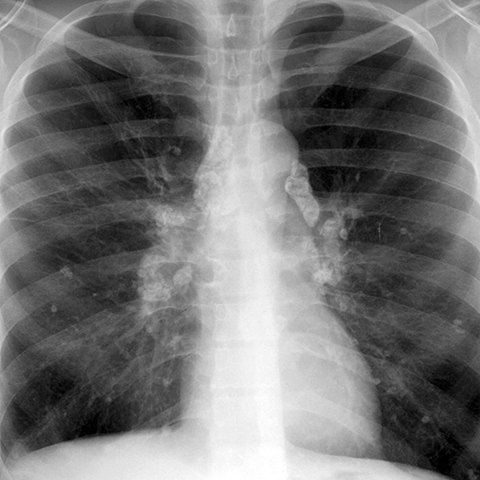

Calcified Hilar Nodes, Remote Granulomatous Infection [1 of 4]